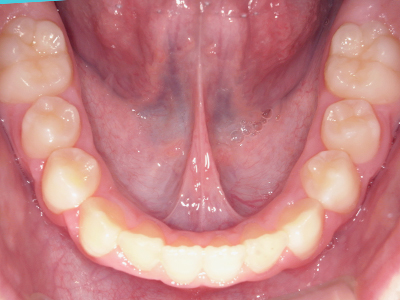

歯並びの相談に来られるお子様は、口呼吸をしているケースが多く、これが歯並びに大きな影響を与えています。

↓ - 頬の圧力が上の歯列にかかりやすくなる

↓ - 上あごが狭くなる

↓ - 下あごが狭くなる・下あごの位置が悪くなる

↓ - さまざまな不正咬合が生じる

ないき歯科クリニックでは、上あごの成長不足を補い、鼻呼吸を獲得しつつ歯列を整え、将来のお口をより健康な状態にすることをゴールに定める矯正治療をおこなっています。